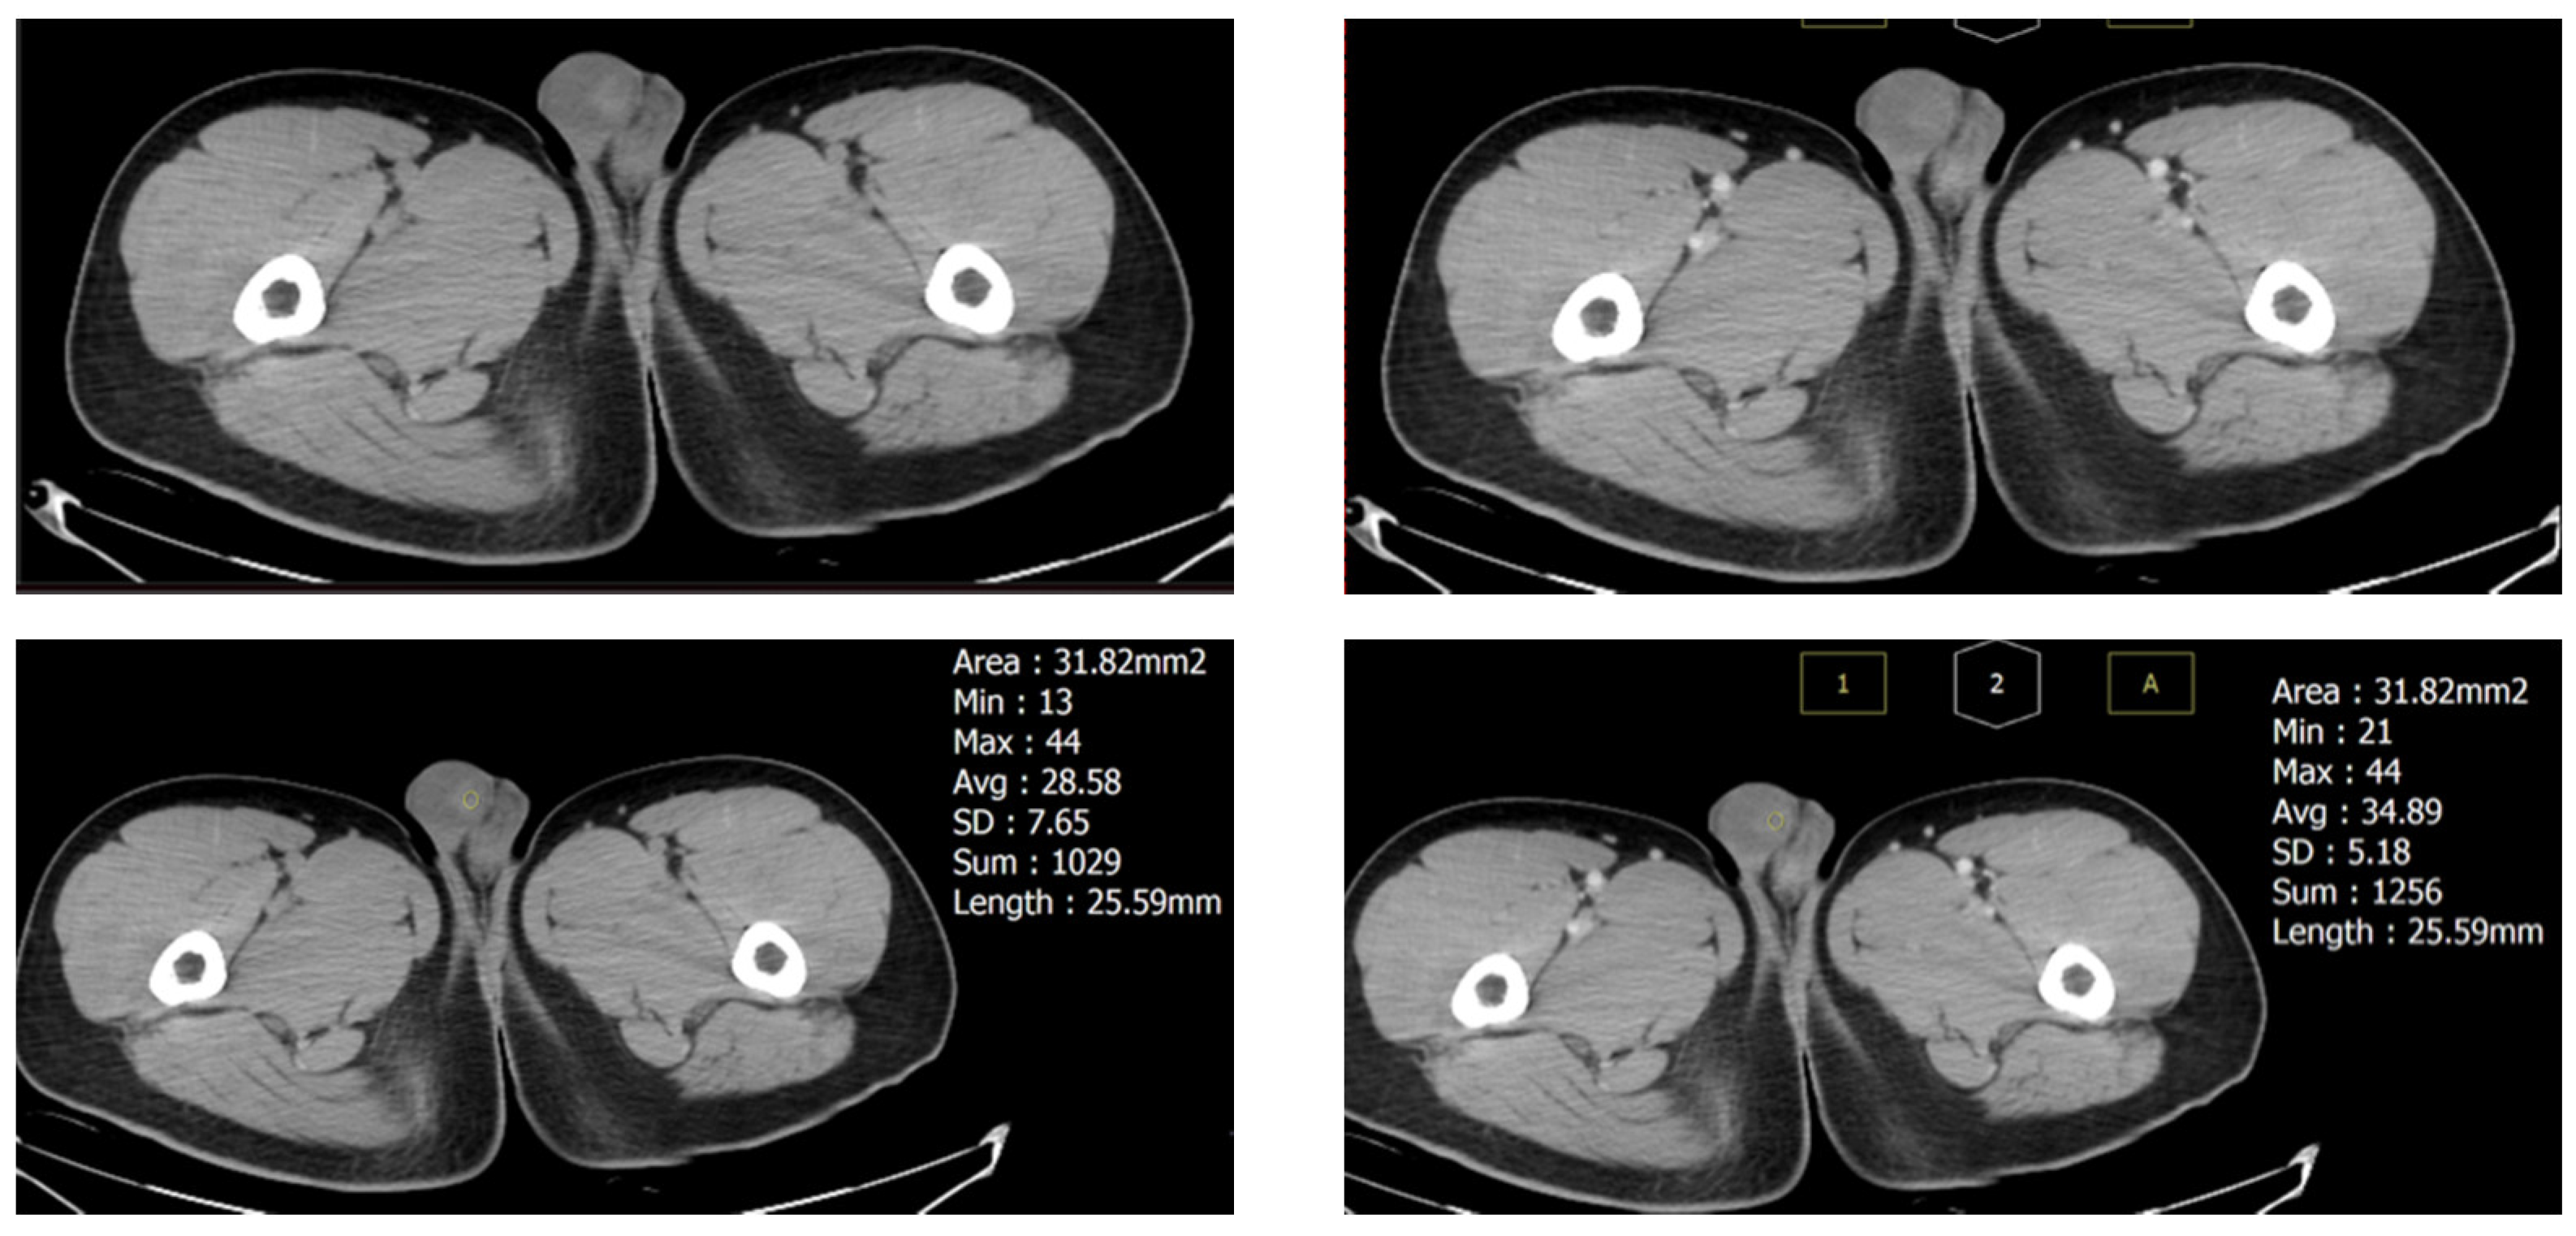

2. Case Presentation